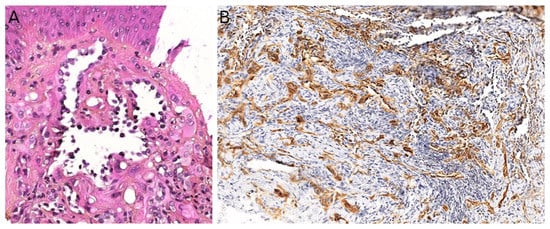

3.2. Papillary Intralymphatic Angioendothelioma (PILA)/Retiform Hemangioendothelioma

3.3. Pseudomyogenic Haemangioendothelioma